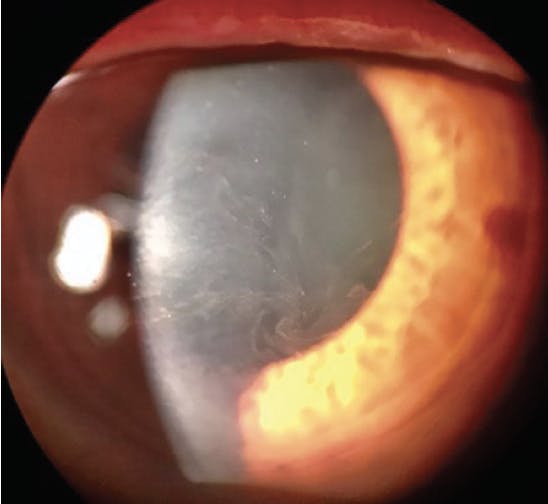

A rarer side effect of netarsudil is reticular bullous epithelial edema, also referred to as corneal honeycombing (Figure 2). In a case series, patients developed reduced visual acuity, inferior bullous keratopathy, stromal edema, and mild anterior chamber inflammation 2 to 4 weeks after starting therapy with netarsudil.21 Significant edema was concentrated under the corneal epithelium. This side effect usually manifested in patients who had predisposing risk factors for developing corneal edema and/or inflammation (eg, history of pseudophakic bullous keratopathy, glaucoma drainage device implantation, etc.). Clinicians should therefore consider these factors before prescribing netarsudil. The edema generally resolved after drug cessation, but the visual acuity decline was permanent.

Figure 2. OCT scan of a cornea with reticular bullous epithelial edema.

Courtesy of Robert Schultz, MD